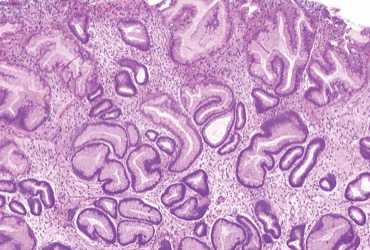

description

By Prateek Sharma, MD, with Jillian Mock This edition of Sharma’s Endoscopy Insights focuses on gastric hyperplastic polyps and the role of prophylactic clipping during colorectal endoscopic submucosal dissection. Gastric hyperplastic polyps have bee... [4102 chars].. reed more